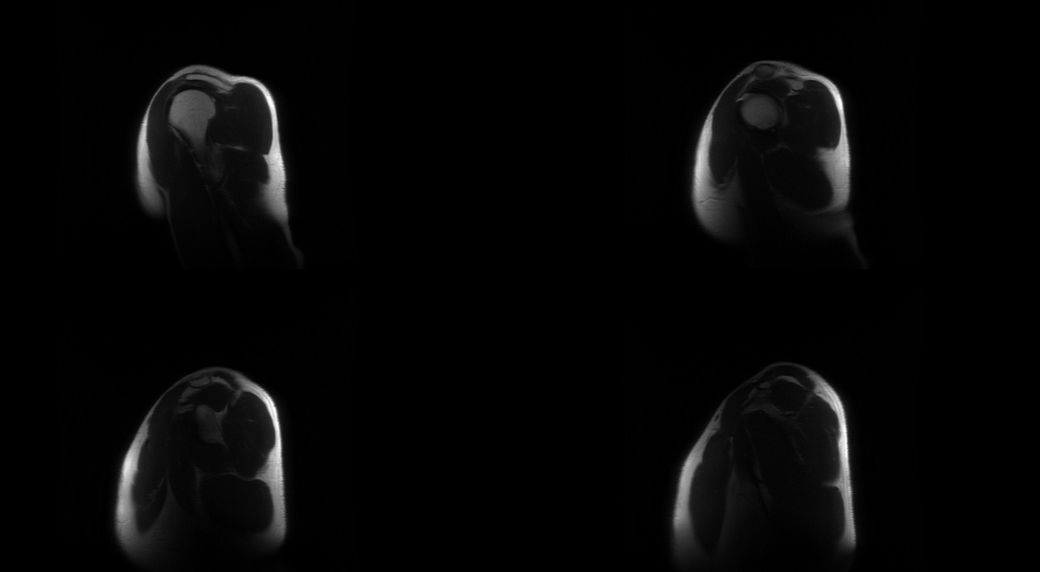

어깨 통증이 있어 mri를 찍었습니다

6월부터 어깨 통증이 있어 초음파 검사를

했고 염증이 있다하여 스테로이드 주사를 맞아 호전됐지만 한달뒤에 계속 재발하여 의사선생님이 mri를 찍어보자고 해서 찍었습니다 한 번 보시고 상태가 어떤지 알려주시면 감사드리겠습니다

• 1번 째 사진

• 2번 째 사진

• 3번 째 사진

• 4번 째 사진